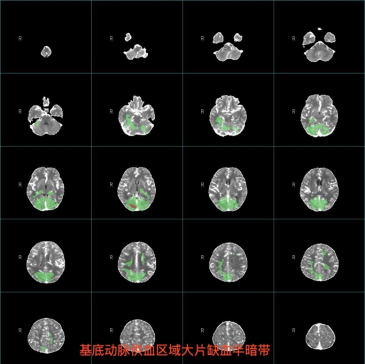

时间就是大脑,每延迟一分钟,大脑就失去190万个神经元。患者的CTP(脑灌注成像)结果显示,虽然基底动脉已经闭塞,但大脑后部仍有大片缺血但尚未坏死的“半暗带”——这是我们可以拯救的脑组织,也是我们必须行动的信号。